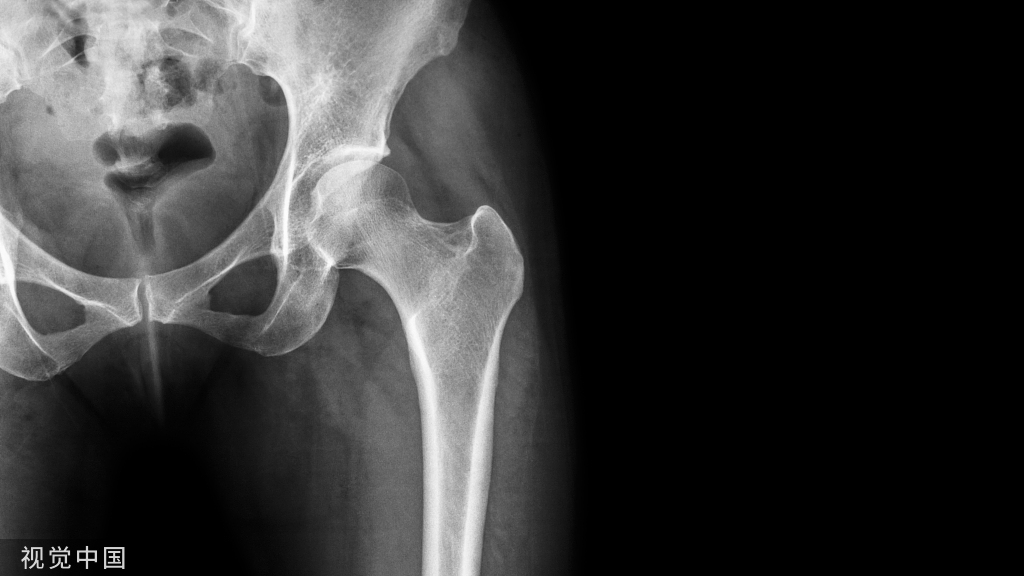

髋部骨折类型

不同类型的髋部骨折手术方式不同,造成的组织创伤不同,导致的术后疼痛也有一定的差异。